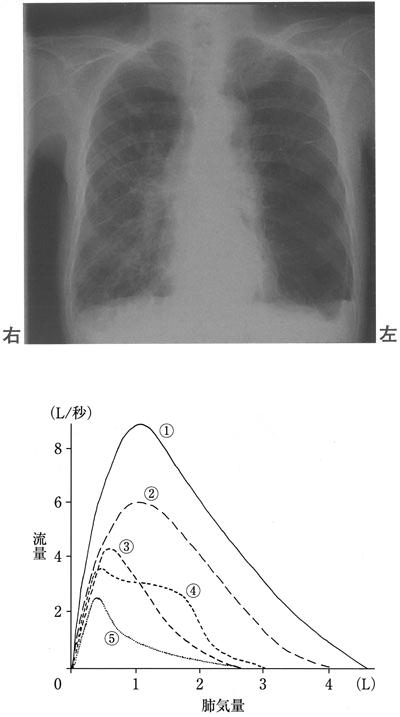

75歳の男性。身長170 cm、体重48 kg、BMI 16.6。約10年前から呼吸困難が出現し自宅近くの医院で加療していた。徐々に呼吸困難感が増悪してきており、50 m程度の連続歩行で呼吸困難感のため休息が必要である。動脈血ガス分析PaO2 65 Torr、PaCO2 48 Torr、肺機能検査%VC 81%、FEV1% 31%であった。患者の胸部エックス線写真を示す。この患者の運動療法を中止すべき状態として最も適切なのはどれか。

75歳の男性。身長170 cm、体重48 kg、BMI 16.6。約10年前から呼吸困難が出現し自宅近くの医院で加療していた。徐々に呼吸困難感が増悪してきており、50 m程度の連続歩行で呼吸困難感のため休息が必要である。動脈血ガス分析PaO2 65 Torr、PaCO2 48 Torr、肺機能検査%VC 81%、FEV1% 31%であった。患者の胸部エックス線写真を示す。予測されるフローボリューム曲線として最も適切なのはどれか。